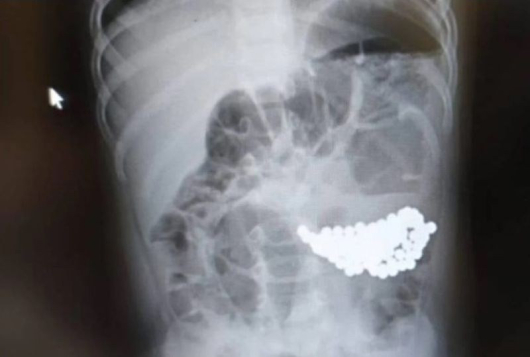

Хирурзите на Московската детска болница № 9 "Г. Н. Сперански" извадиха 117 магнитни топчета от стомаха на едногодишно дете. Това се съобщава на уебсайта на Министерството на здравеопазването в Москва.

Родителите веднага се обадили на линейка. Лекарите решили да прегледат и двете деца. Момичето било пуснато у дома веднага след рентгеновата снимка; в стомаха й не било открито нищо опасно. Но по-малкият й брат спешно е преместен в операционната - снимката показвала, че в стомаха му се е събрала огромна буца магнитни топчета.

"Със специални инструменти отстранихме цели 117 малки чужди предмети от стомаха на пациента! За щастие, магнитните топки, привлечени една към друга, не са имали време да нарушат функцията на стомаха. След операцията на бебето е предписана антибактериална, инфузионна терапия", каза началникът на отделението по гнойна хирургия No2 Нодари Зурбаев.